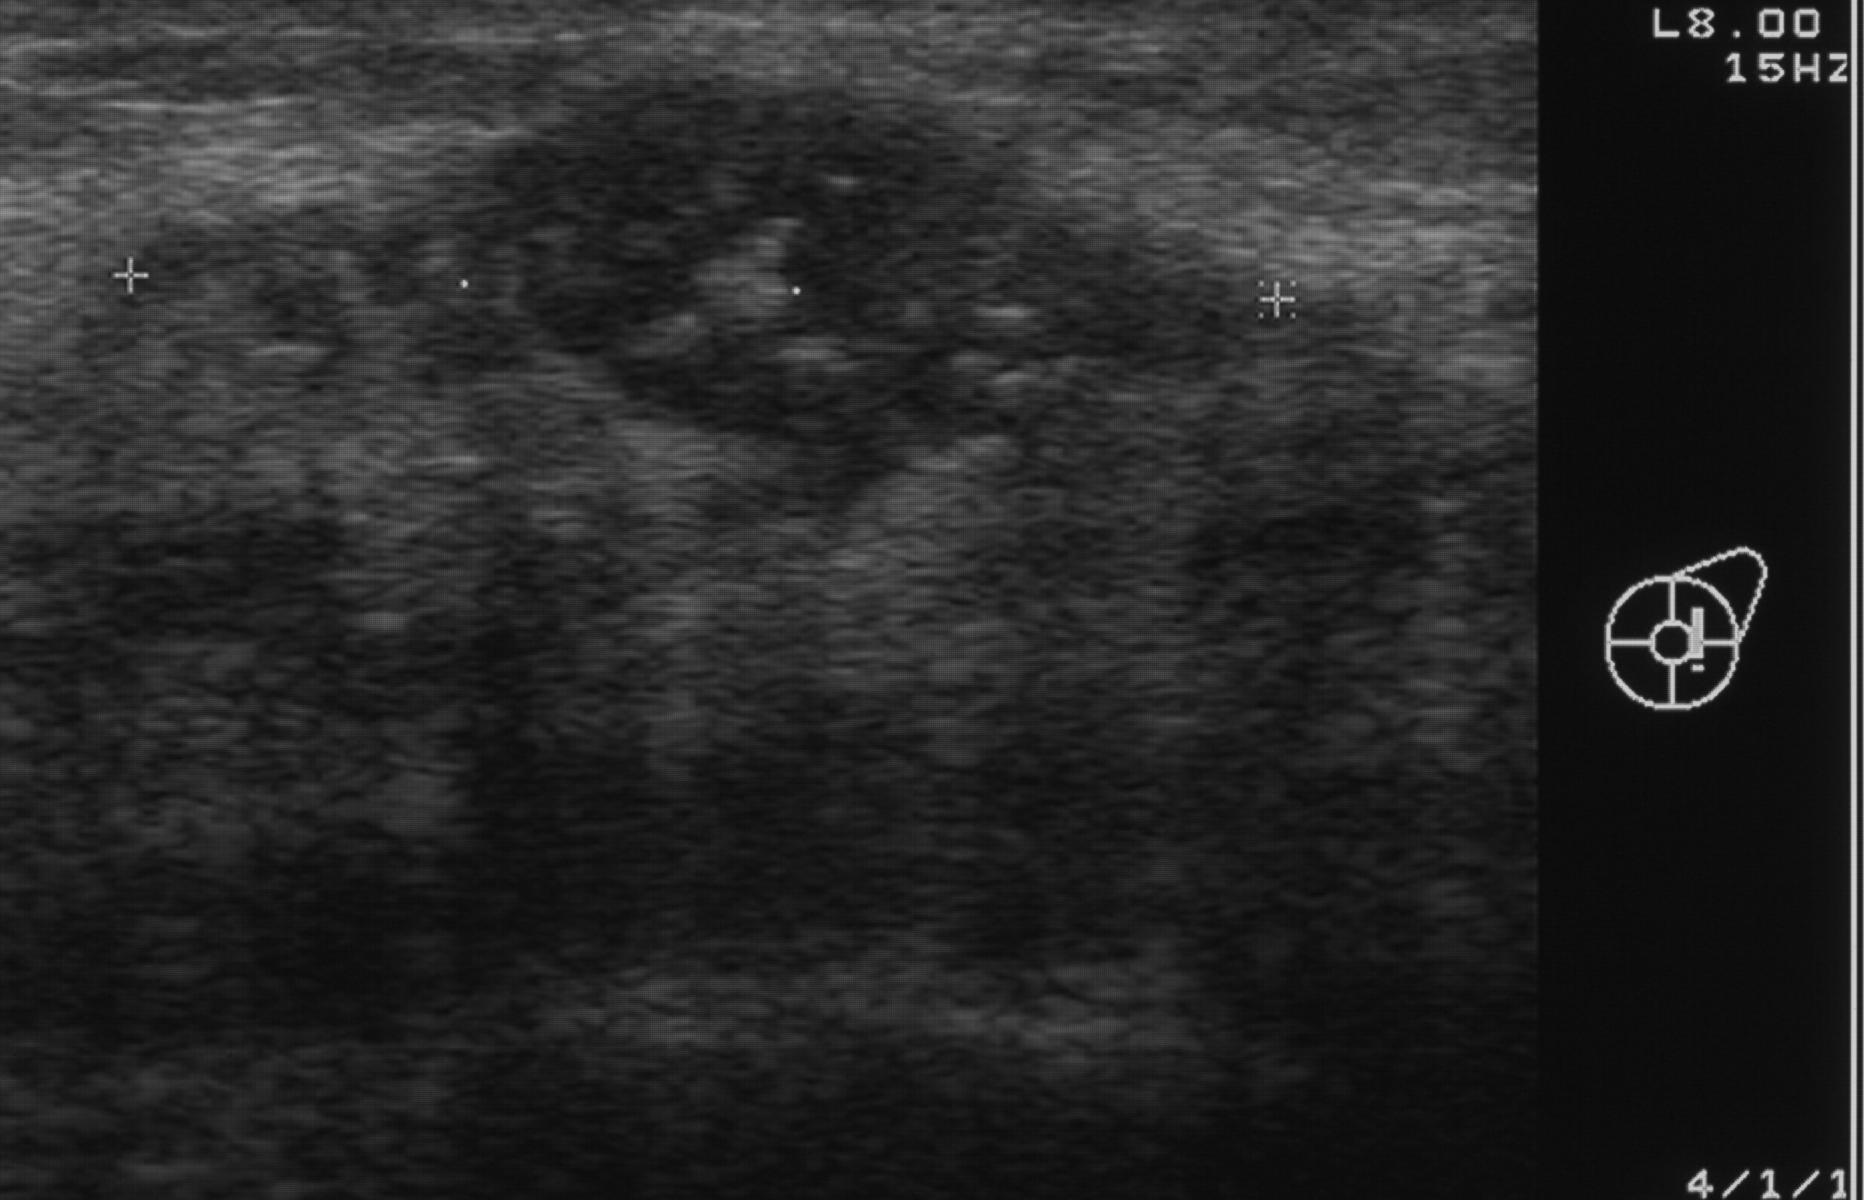

Ecografia mammaria

Immagine 1/1